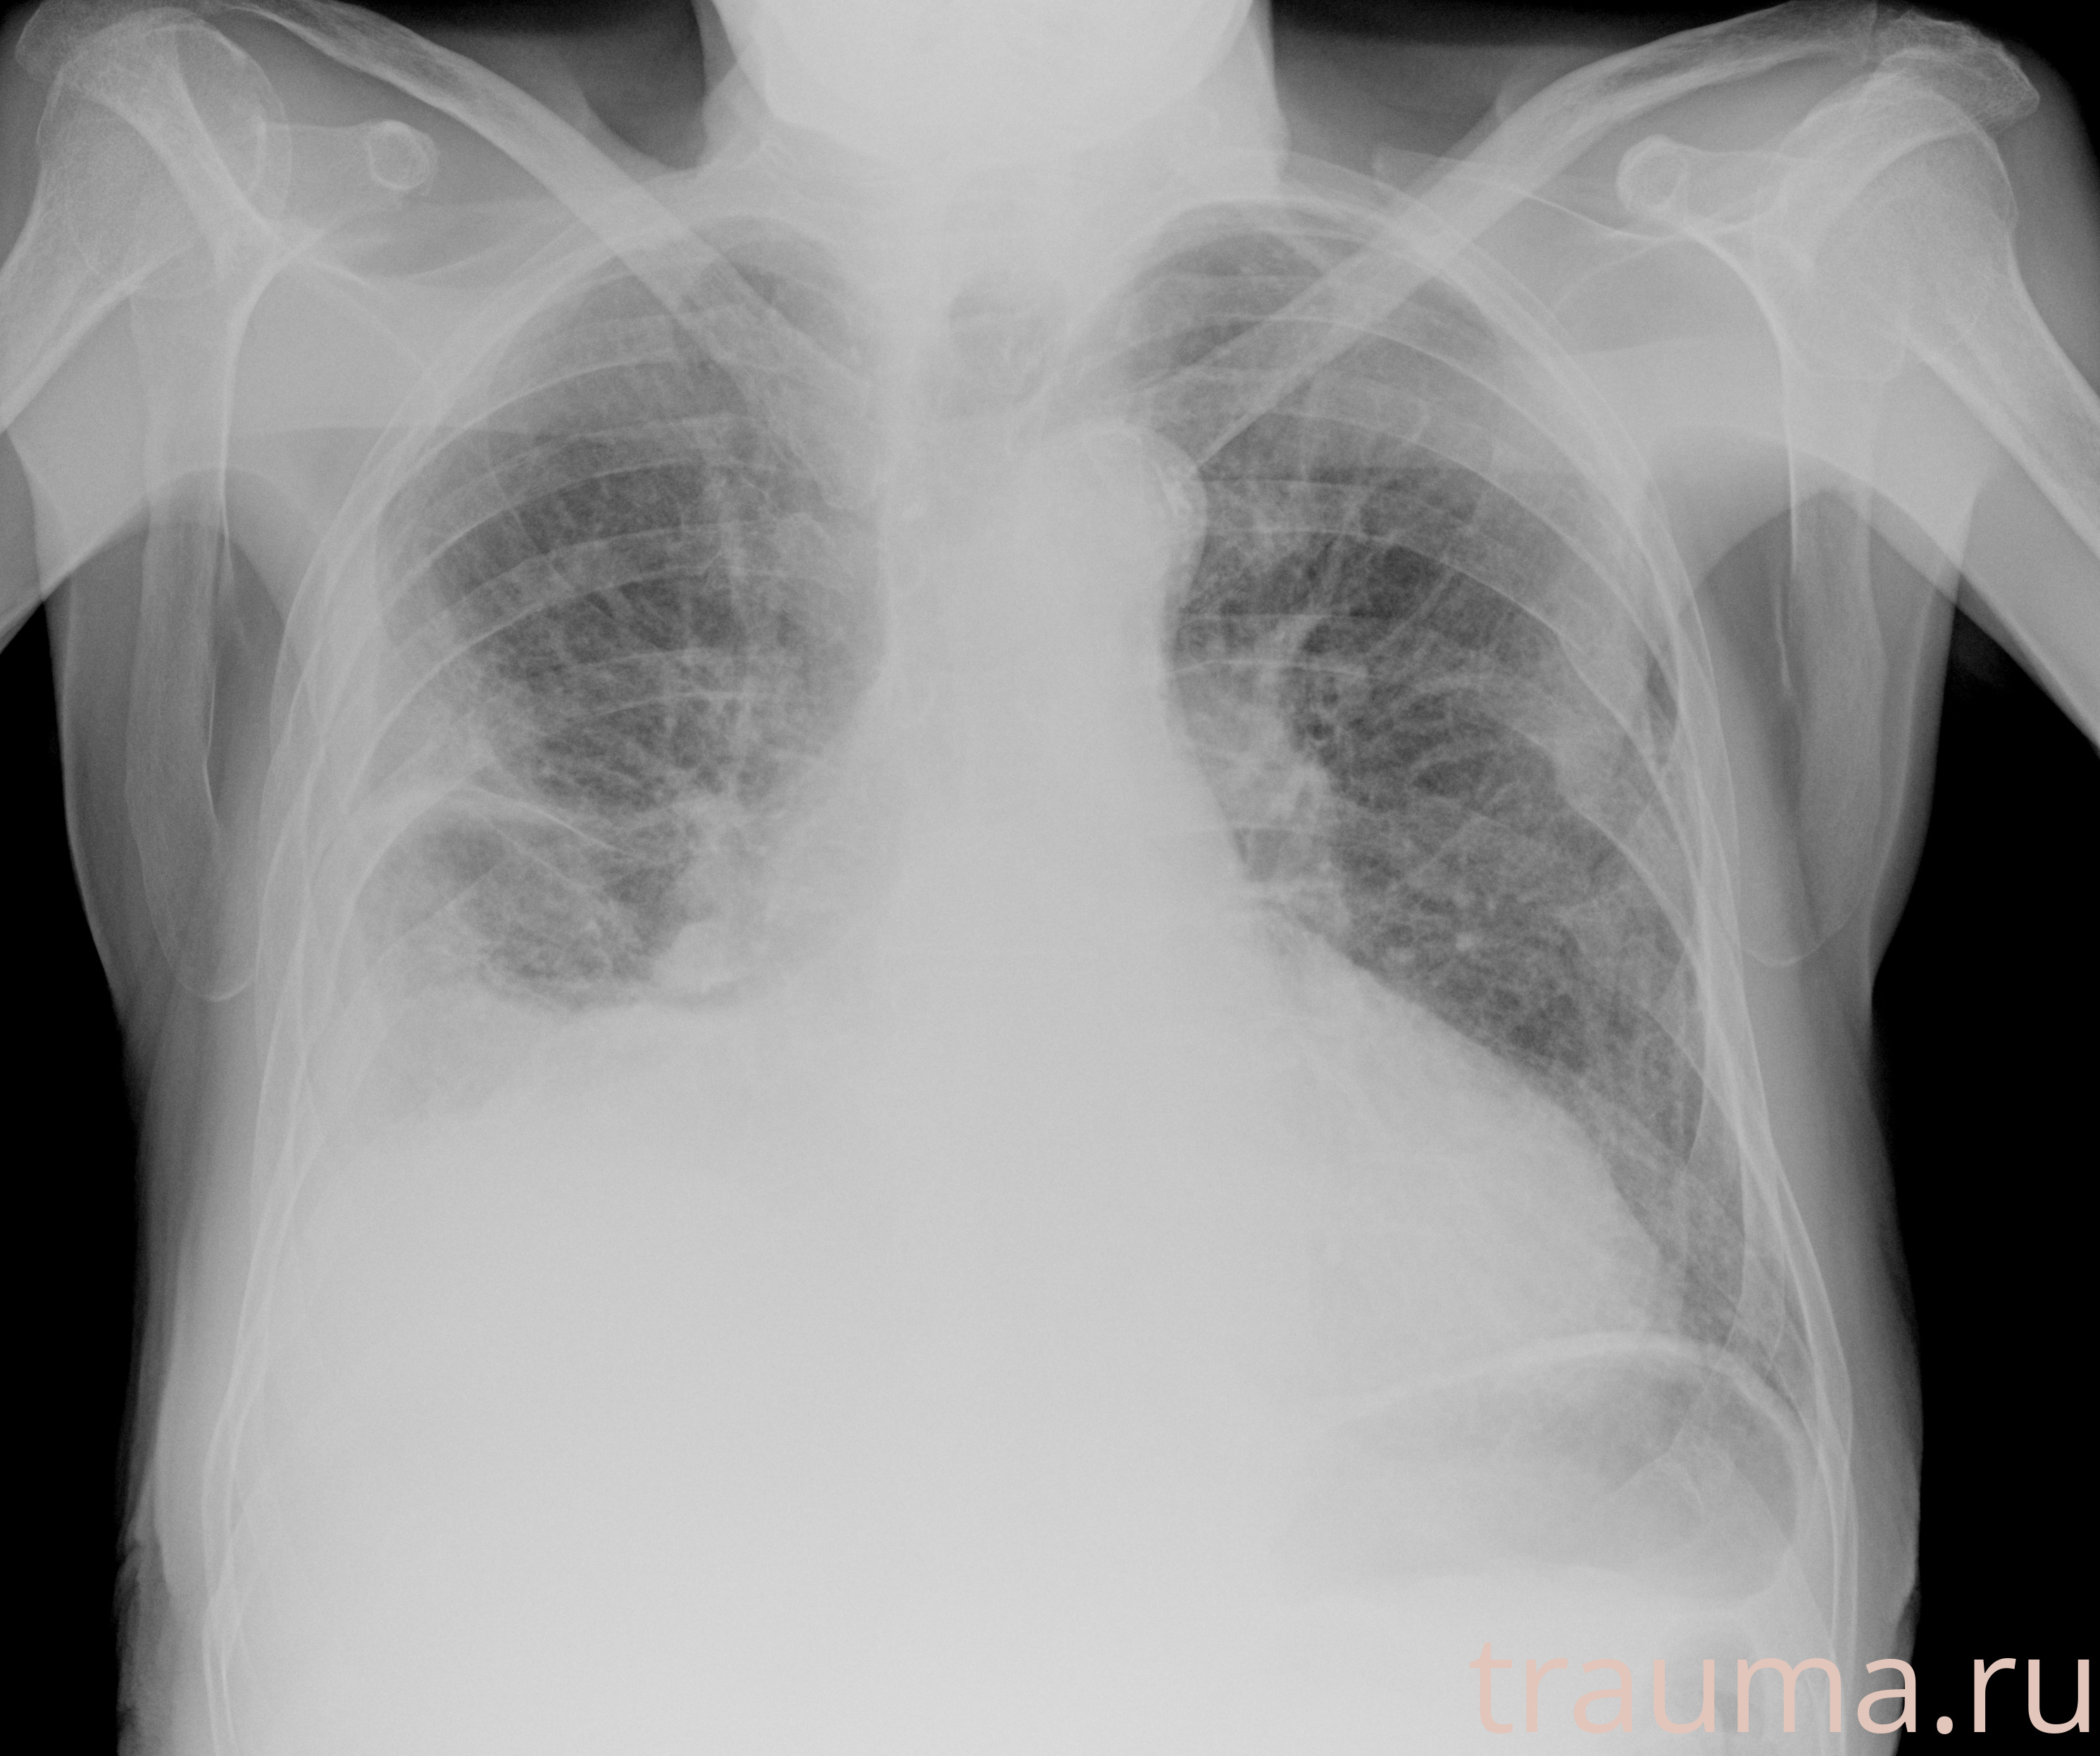

Рентгенограммы

Рентген на дому: по вашему адресу приезжает врач-рентгенолог, травматолог-ортопед с мобильным рентгеновским аппаратом, проводит диагностику травмы или заболевания, делает необходимые рентгенограммы, дает рекомендации по дальнейшему лечению. Получить качественные снимки в домашних условиях возможно благодаря уникальной методике, разработанной МосРентген Центром для института  Склифосовского

при переломе шейки бедра и пневмонии от компании МосРентген Центр - партнера Института имени Склифосовского